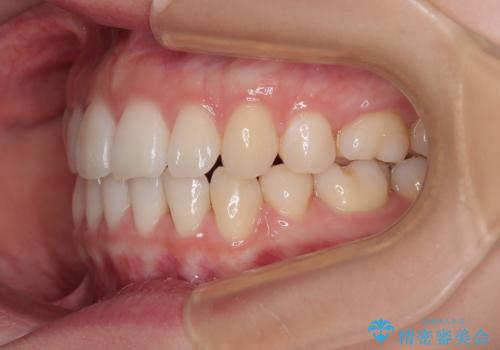

横顔の印象を変えたい ワイヤー装置での抜歯矯正

- 口元の突出感と上下前歯のズレを気にして来院された患者様です。

舌の突出癖により上下の前歯は非接触となっている状態でした。

舌のトレーニングを行わないと上下前歯の接触達成は困難であるため、トレーニングをしっかりと行っていただきながら、治療を進めて行くこととしました。

突出感改善のため、上下左右の第一小臼歯4本を抜歯し、ワイヤー装置にて矯正治療を行うこととしました。

舌のトレーニングをしっかりと行ってくださり、予定通りの期間で理想的な仕上がりを達成することができました。